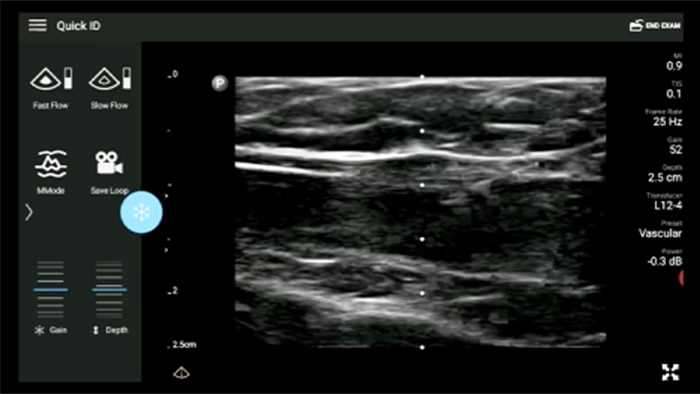

Lumify L12-4 broadband linear array transducer

• 4 to 1 MHz extended operating frequency range • 2D, color Doppler, M-mode, advanced XRES and multivariate harmonic imaging • High-resolution imaging for abdominal and cardiac applications: Cardiac, OB/GYN, Lung, Abdomen and FAST imaging preset optimizations